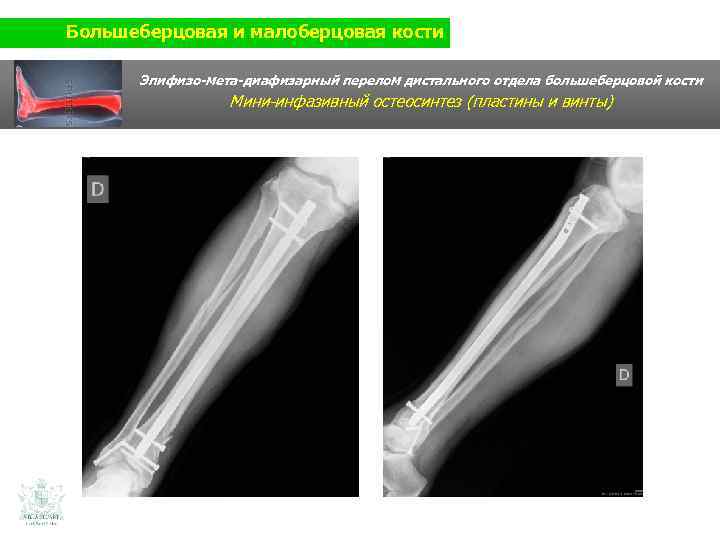

Большеберцовая и малоберцовая кости Клинический случай (большеберцовая и малоберцовая кости) Мужчина 60 ти лет Травма нижней конечности (авария на мотоцикле)

Большеберцовая и малоберцовая кости Эпифизо-мета-диафизарный перелом дистального отдела большеберцовой кости

Большеберцовая и малоберцовая кости Эпифизо-мета-диафизарный перелом дистального отдела большеберцовой кости Мини-инфазивный остеосинтез (пластины и винты)